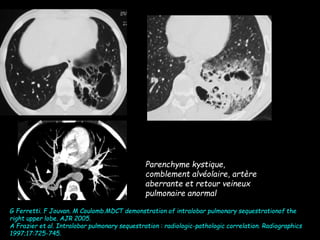

Parenchyme kystique,

comblement alvéolaire, artère

aberrante et retour veineux

pulmonaire anormal

G Ferretti. F Jouvan. M Coulomb.MDCT demonstration of intralobar pulmonary sequestrationof the

right upper lobe. AJR 2005.

A Frazier et al. Intralobar pulmonary sequestration : radiologic-pathologic correlation. Radiographics

1997;17:725-745.